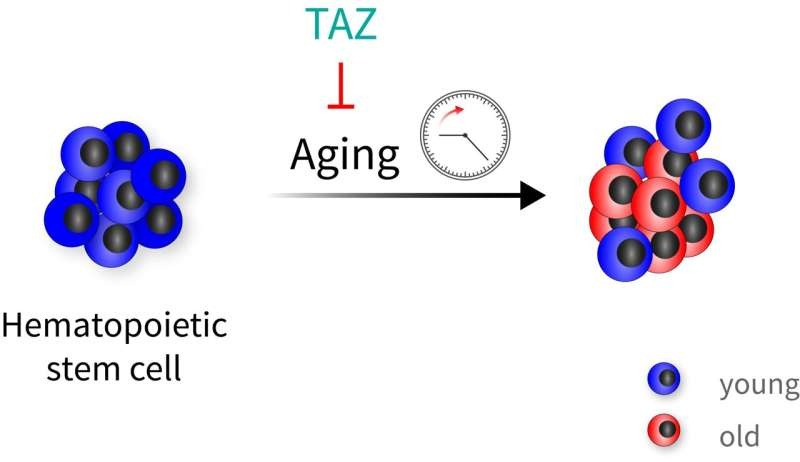

старение

стволовые клетки

омоложение